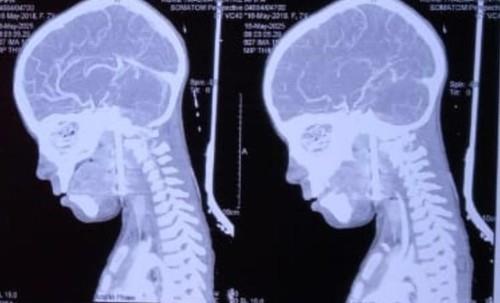

Dečaku se tokom igranja ekser od 8 cm zabio u glavu: Lekari se smrznuli kad su videli snimak, ono što je potom usledilo je čudo (FOTO)

dečak ekser profimedia-1005203979.jpg

2 / 4

TIM / Jam Press / Profimedia